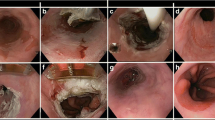

4.4 Cryotherapy

Cryotherapy is based on the principle of ablating Barrett’s tissue by application of a cryogen leading to extremely cold temperatures. Repeated cycles of rapid freezing followed by slow thawing lead to cell membrane rupture. Delayed injury includes tissue anoxia due to the loss of microcirculation and immune-related processes. There are two types of cryotherapy devices commercially available: one is cryospray (CSA Medical) which uses liquid nitrogen delivered at −196 C (Fig. 4.2), and the other is Polar Wand (GI supply) which utilizes carbon dioxide gas cooled to −78 C. A recently developed simplified through the scope focal cryoballoon system (C2 Therapeutics) is being studied for Barrett’s ablation. Since cryoablation does not require any contact, it is useful for patients with tortuous esophagus and nodular uneven mucosal surface.

4.4.1 Technique

Cryotherapy is performed by passing the catheter through the accessory channel of an endoscope, and the tip of the catheter is held 5–10 mm away from the target tissue. The foot pedal is depressed, which triggers the release of the cryogen. The cryogen is sprayed onto the target tissue until it turns white, which means that freezing has taken place. This generally occurs after 10–15 s of application. Thawing usually takes place within 10–30 s. The same area is typically subjected to the freezing–thawing cycle 3 or 4 times to achieve ablation. In cryospray system, a decompression tube is used to evacuate the excess gas from the stomach, whereas in Polar Wand system, suction catheter is attached to the tip of the endoscope.